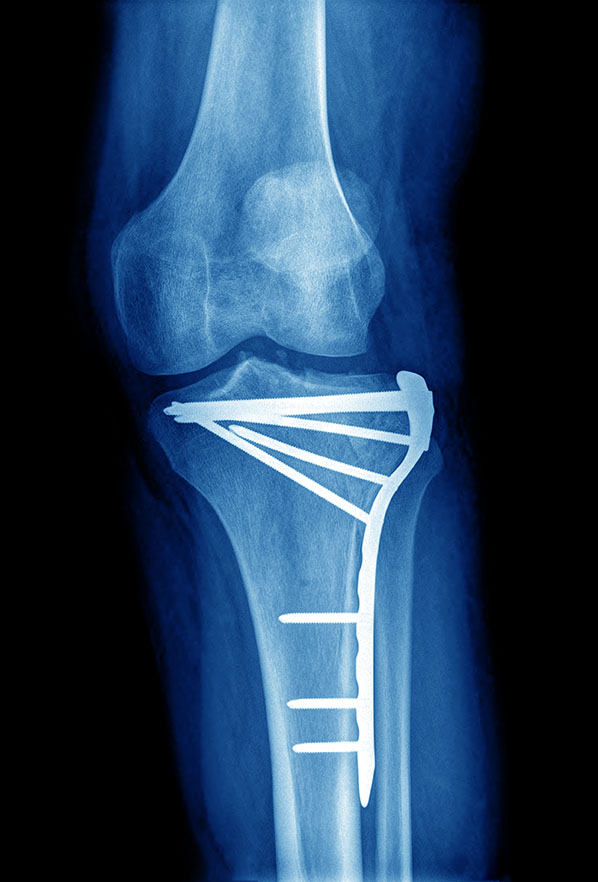

From drdavidgeier.com

Can I play sports with a plate and screws in my leg? Dr Geier Playing Sports With A Fracture Contact between players (eg, a head, fist, elbow);. Timing of return to sports after treatment for an open tibia fracture are unknown, but typically much longer than return after a. Children with distal radius buckle fractures may return to sport by 4 weeksafter initial injury, sooner than recommended. In addition, at 1 year, female. What they do want is to. Playing Sports With A Fracture.